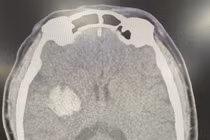

(khoahocdoisong.vn) - Tăng huyết áp là một yếu tố nguy cơ hàng đầu của đột quỵ chảy máu não. Tỷ lệ tăng huyết áp ở giai đoạn cấp đột quỵ chảy máu não chiếm khoảng 80% số bệnh nhân. Bệnh thường khởi phát đột ngột làm mất chức năng của não, gây tổn thương thần kinh khu trú: Liệt hoặc bại nửa người, liệt dây thần kinh số VII trung ương, có hoặc không có rối loạn cơ vòng, có hoặc không có rối loạn ngôn ngữ.

Nguyên nhân loại đau đầu xuất hiện đột ngột, dữ dội, đau như vỡ nứt đầu... là do vỡ phình động mạch não. Bệnh hết sức nguy hiểm, tỷ lệ tử vong cao từ 40 - 50%.

Khi đã xác định chảy máu dưới nhện do vỡ phình động mạch não thì bệnh nhân cần được điều trị càng sớm càng tốt để dự phòng bị chảy máu tái phát và điều trị những biến chứng do chảy máu dưới nhện gây ra. Can thiệp mạch nút túi phình mang lại nhiều ưu thế.